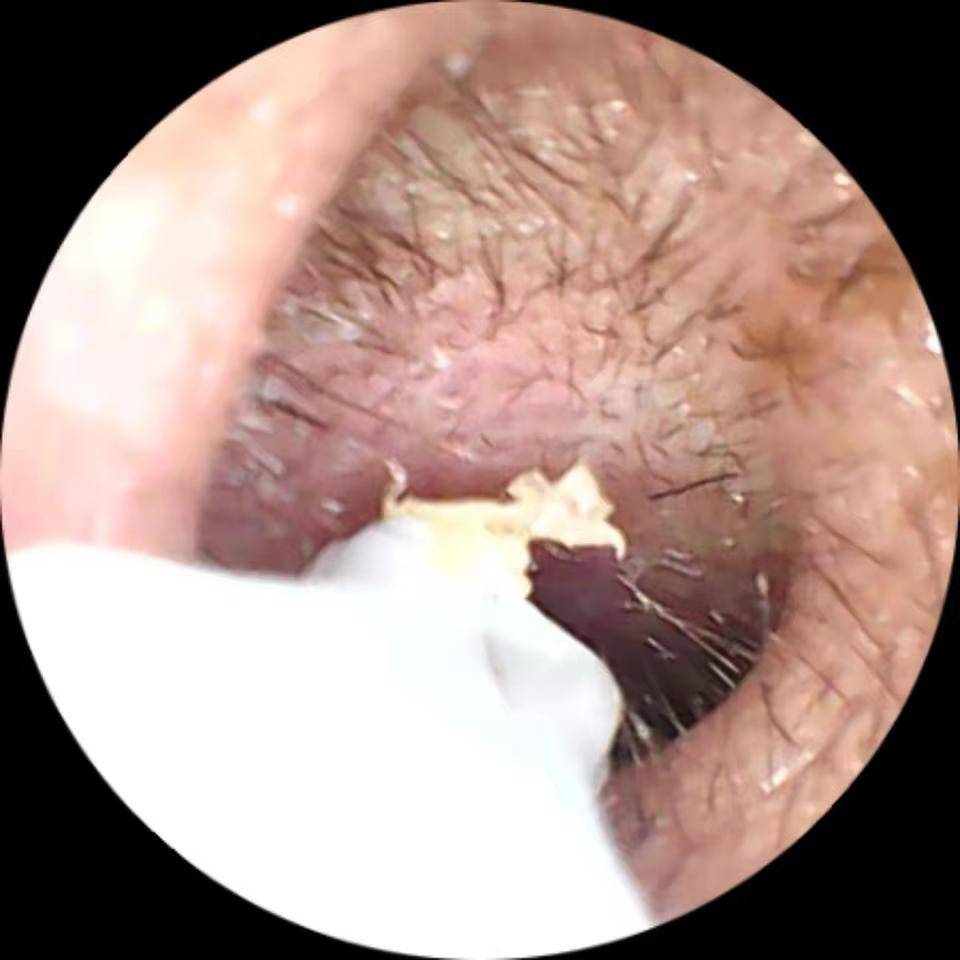

Camear е идеалният инструмент за всички, които търсят модерен, прецизен и лесен за употреба ушен чистач! Използването му е истинска детска игра. Благодарение на вградената си камера с висока разделителна способност, можете да видите вътрешността на ухото си в реално време директно от смартфона си, за безопасно и перфектно почистване. Меката силиконова накрайник осигурява оптимален комфорт и предотвратява всякакво дразнене. Независимо дали е за лична или семейна употреба, Camear предлага практичен, хигиеничен и напълно безопасен опит.

Прецизно почистване и максимална хигиена

Наблюдавайте вътрешността на ушите си дори в тъмното.